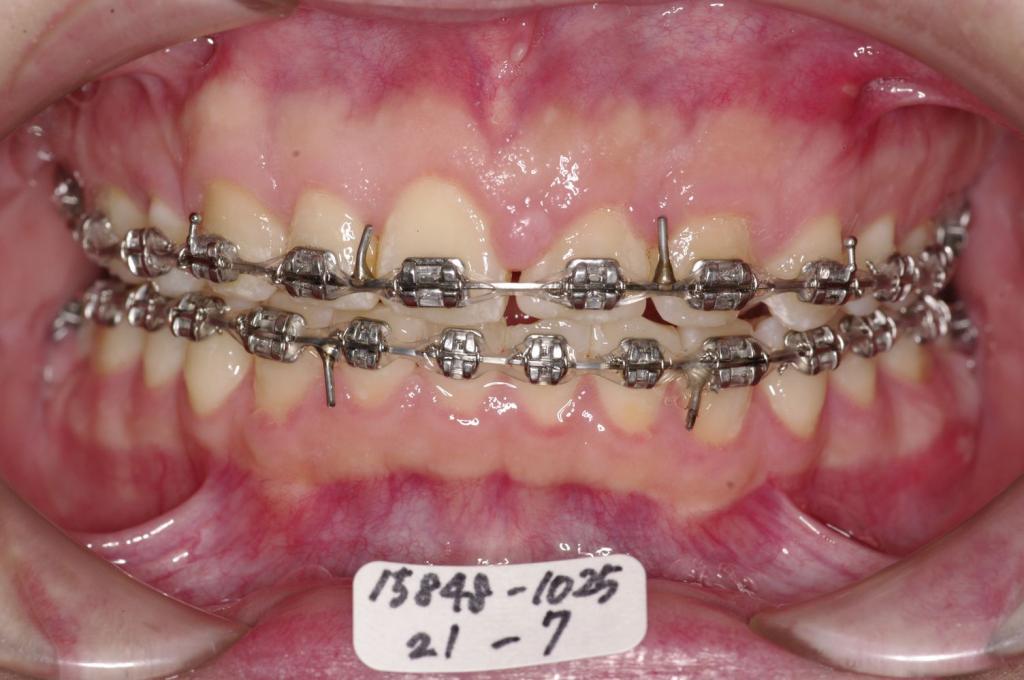

- 前歯、出っ歯・開咬の矯正治療

- 出っ歯